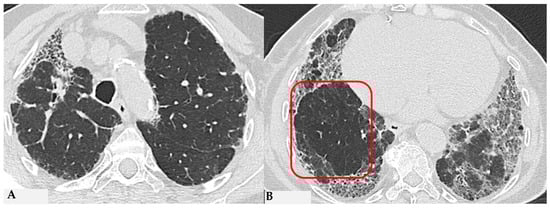

Figure 3.

FHP: chest HRCT (A–D). Upper lobes and right lower lobe are characterized by areas of increased GGO density (green box: (A,D)) within which well-defined bronchiectasis and traction bronchiolectasis, indicative of established fibrotic damage, are observed (green arrows: (B)). Lower lobes extensively affected by mixed alterations, expressing damage to small airways with areas of reduced attenuation suggestive of air trapping (red box: (C)), and confirmed fibrotic damage with honeycombing and traction bronchiectasis (black box; (C)). Pattern of FHP.